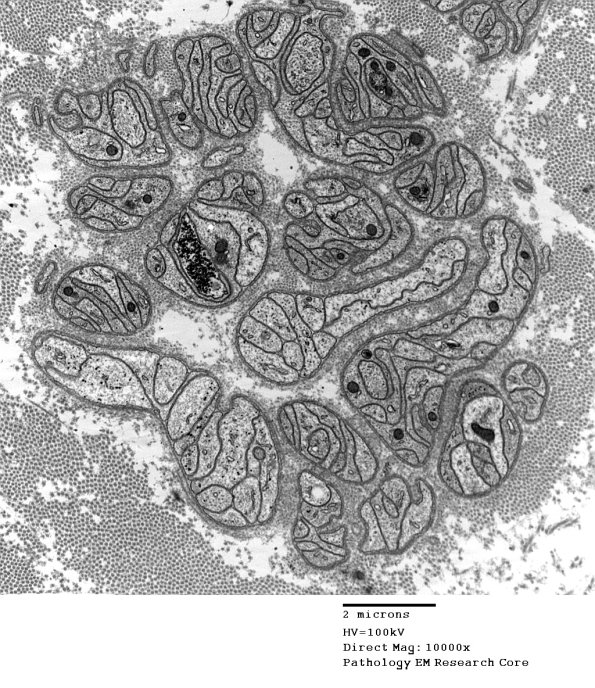

4B2 Axonal Degeneration (Case 16) 039 - Copy

In most cases the Schwann cell processes form long stacked aggregates.